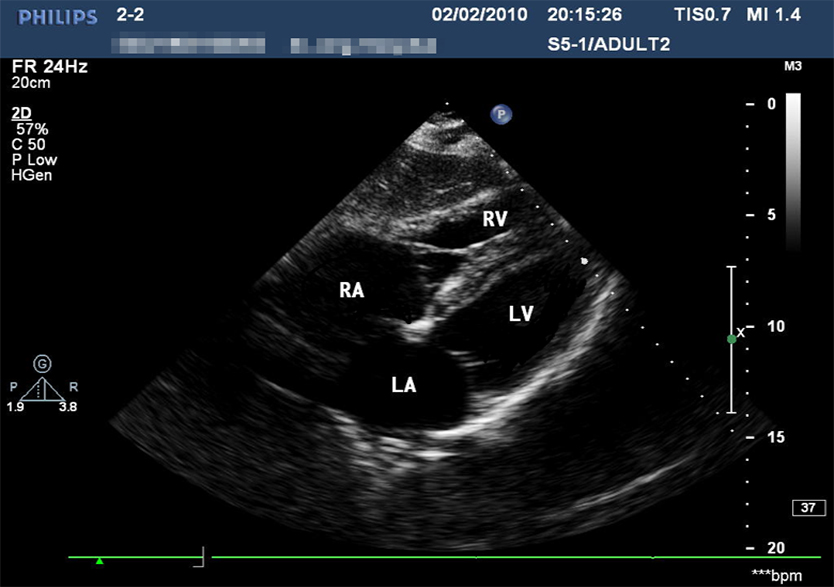

影像系列